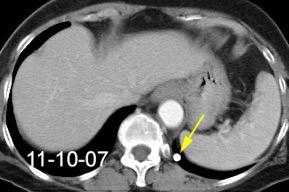

By-pass coronario 21-10-03

Síndrome de afectación postcardiaca (postcardiac injury)

Post infarto 1-7 % (Dressler)

Trauma cerrado Implantación marcapasos

Cirugía cardiaca. 17-31% (Post.pericardiotomía)

3707 pacientes 29 Derrames (0,78%) > de 25% del hemitórax

Todas menos 2 Izdos.

Angioplastia